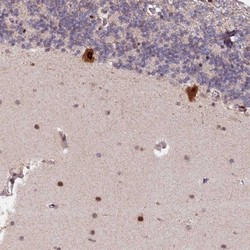

Supportive validation

- Submitted by

- Novus Biologicals (provider)

- Main image

- Experimental details

- Immunohistochemistry-Paraffin: N4BP2L1 Antibody [NBP1-84531] - Staining of human cerebellum shows strong cytoplasmic and nuclear positivity in Purkinje cells.